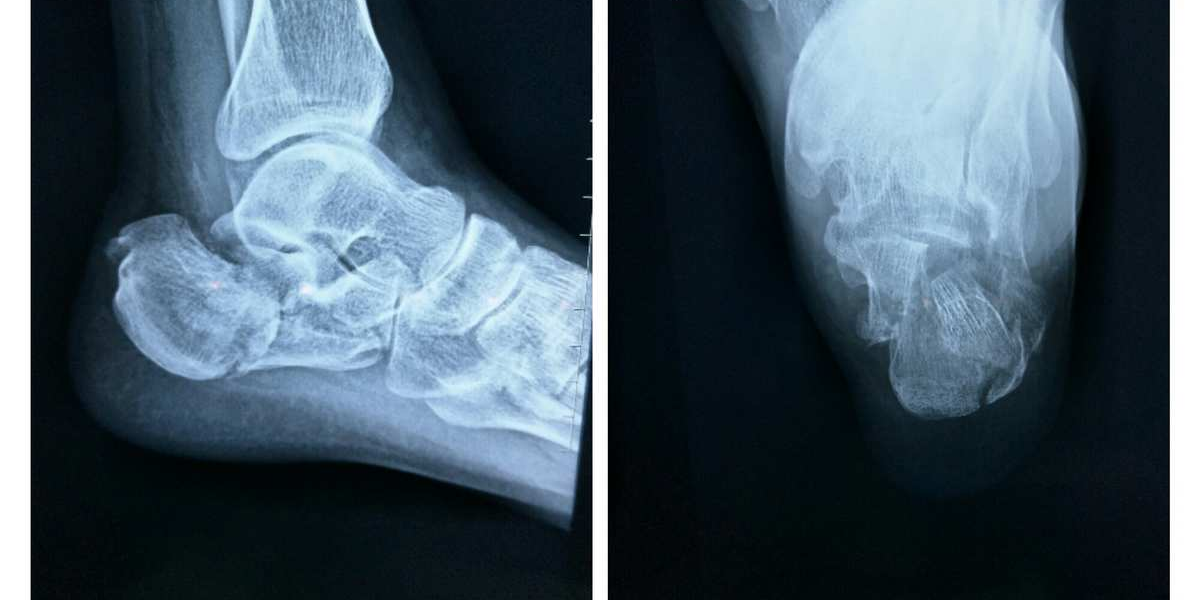

跟骨骨折DR片

此次接受手术的患者因高处坠落致左足跟骨骨折,Sanders分型ⅡB型,骨折碎裂多块、关节面塌陷移位,手术指征明确。考虑患者年轻、对足部功能恢复要求高,骨伤科一病区祝传松主任带领团队经详细术前评估、病情讨论与手术模拟,量身定制全闭合复位微创内固定方案,于患者入院次日顺利完成手术。